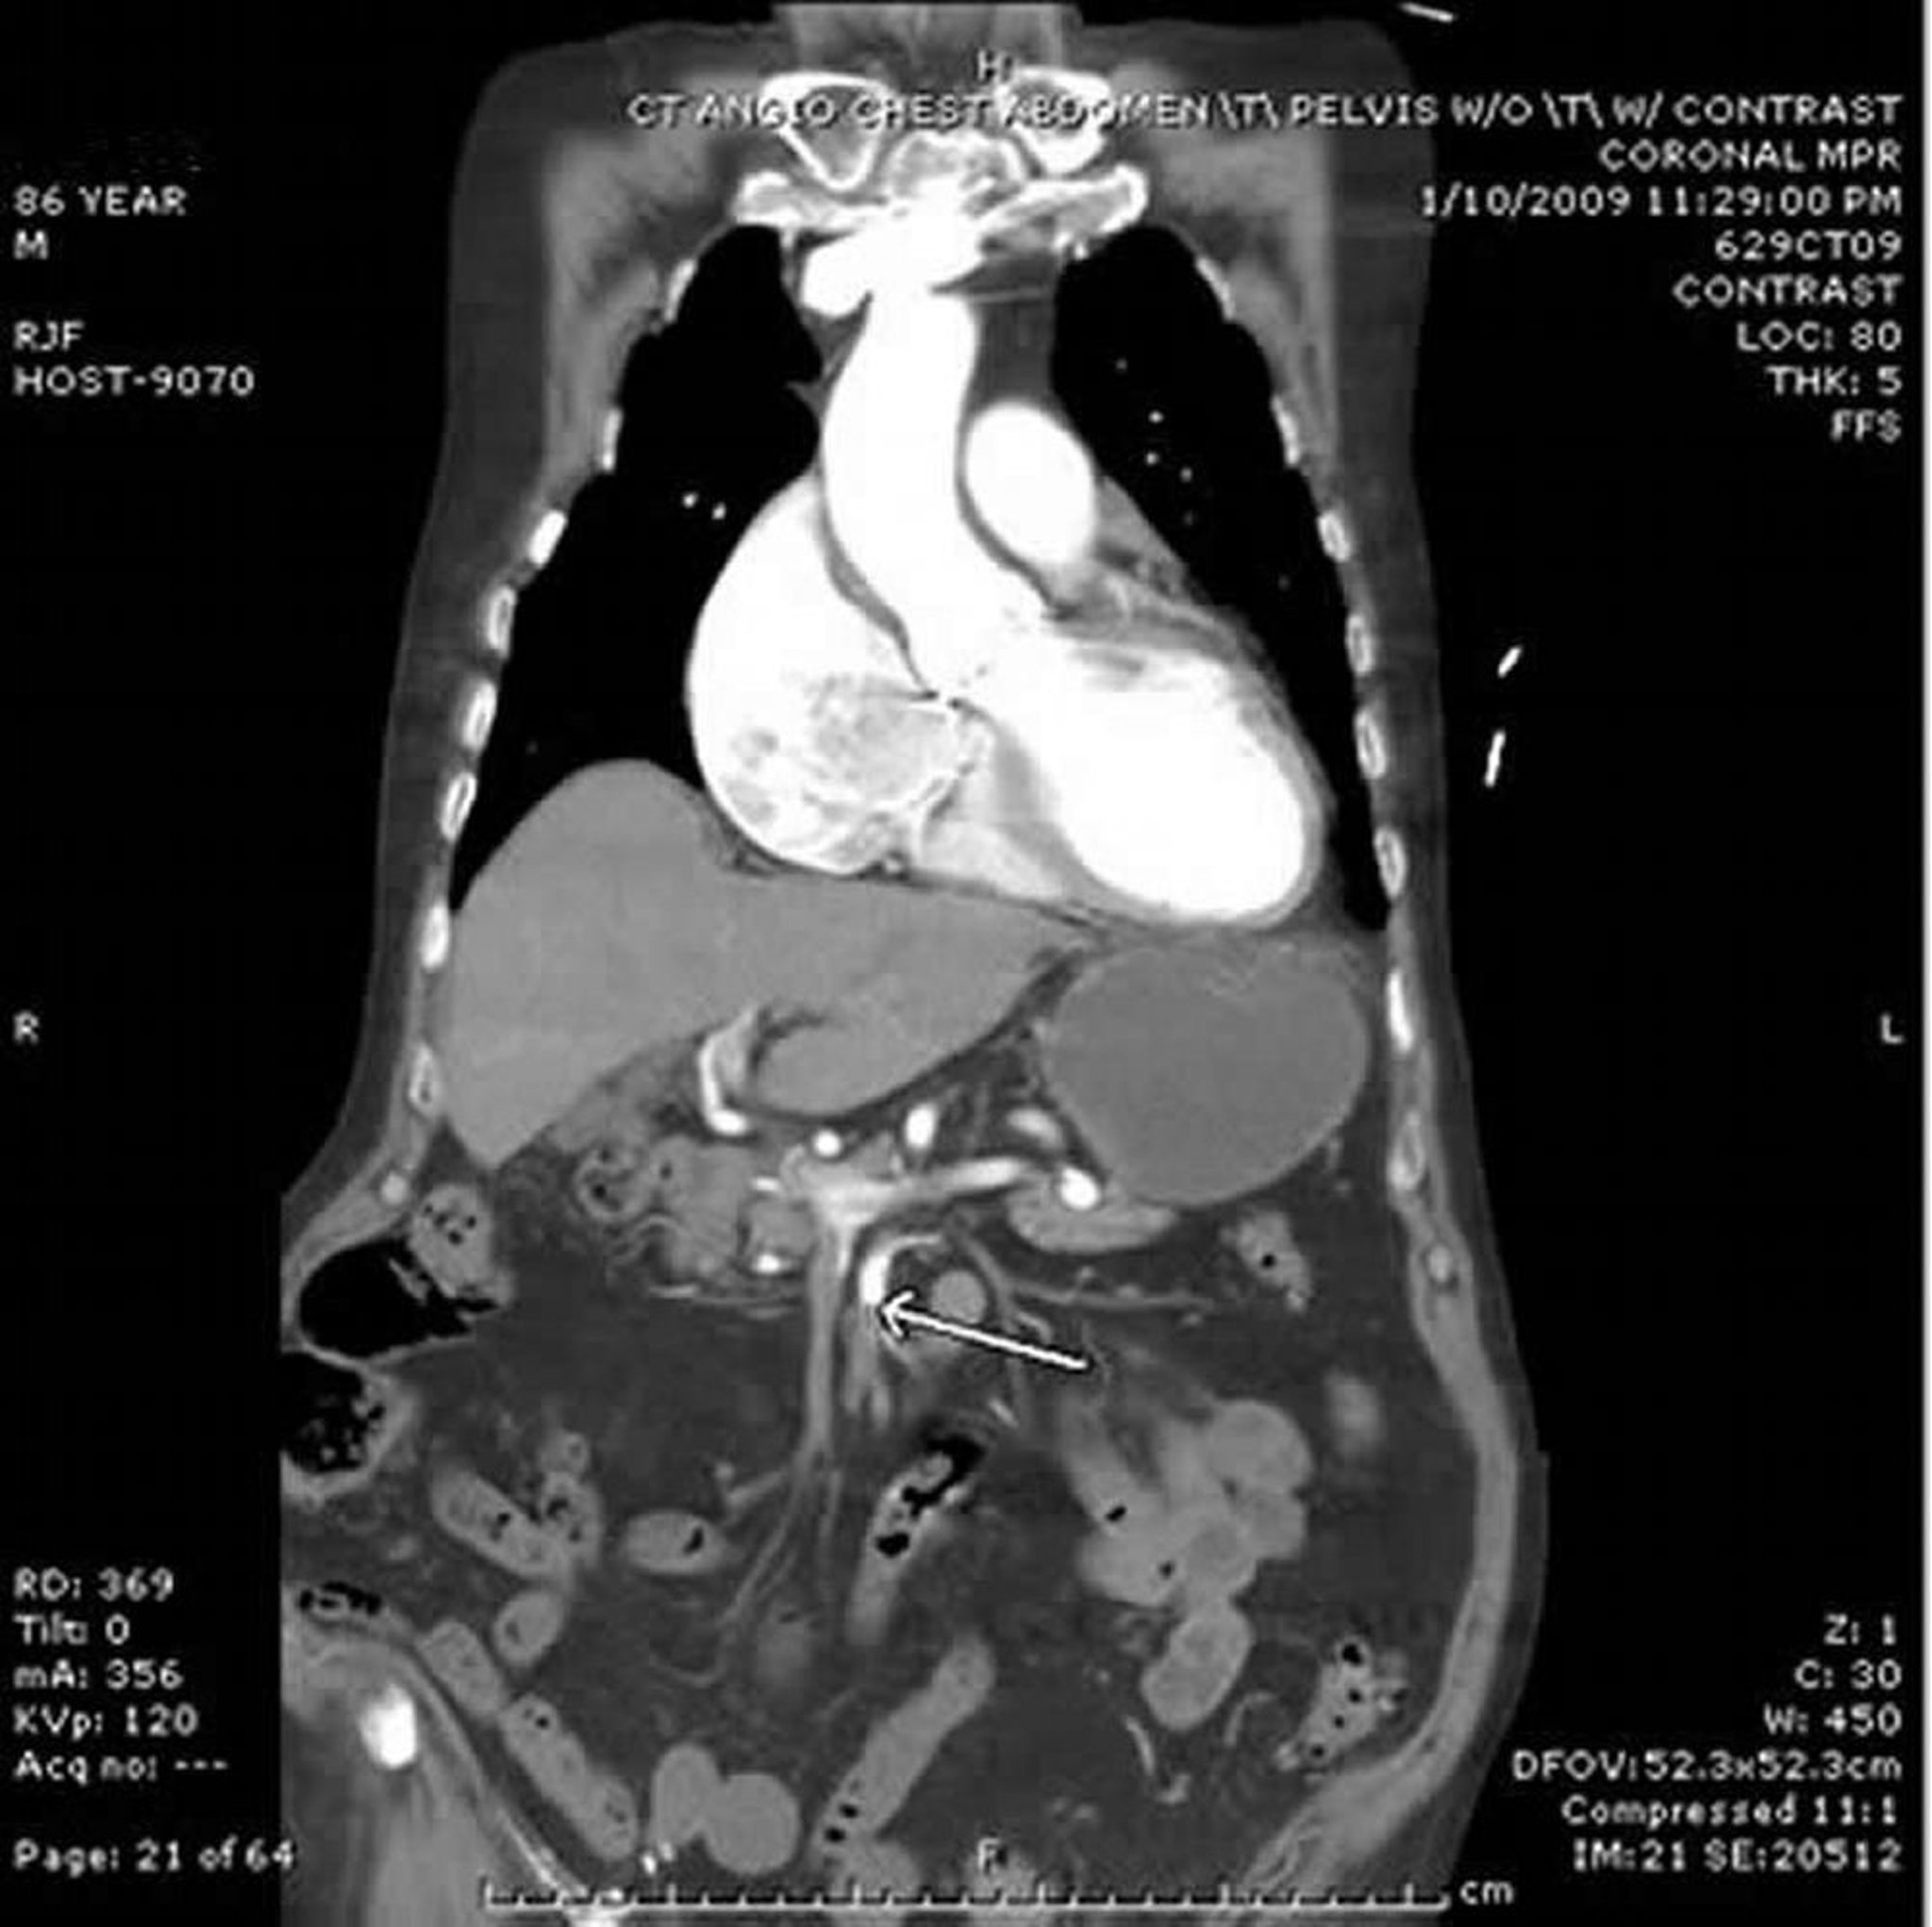

Ischemia mesenterica (Angio-TC)

In questa imagine, la freccia indica l'arteria mesenterica superiore, che mostra una brusca interruzione del contrasto somministrato EV. Si nota un ispessimento dell'intestino tenue nell'addome sinistro. Questo caso di embolia deriva dal cuore di un paziente con fibrillazione atriale.

Image provided by Parswa Ansari, MD.